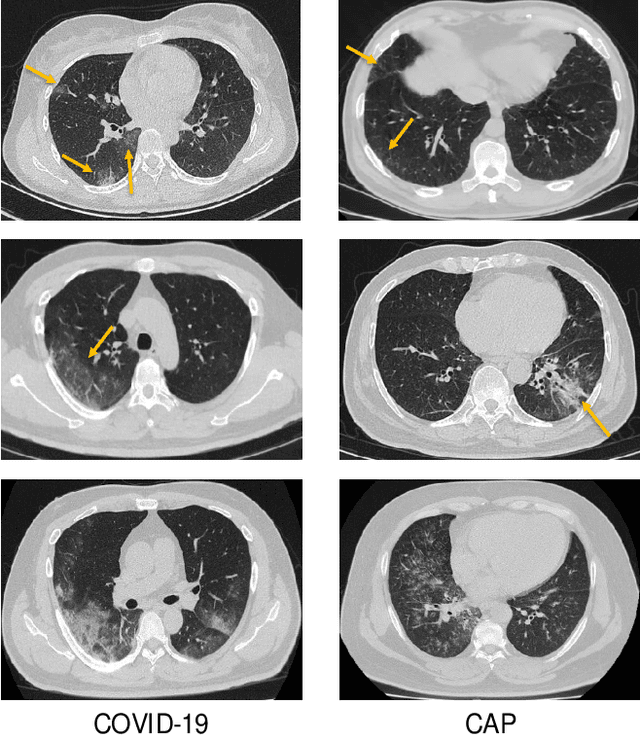

Recently, the outbreak of Coronavirus Disease 2019 (COVID-19) has spread rapidly across the world. Due to the large number of affected patients and heavy labor for doctors, computer-aided diagnosis with machine learning algorithm is urgently needed, and could largely reduce the efforts of clinicians and accelerate the diagnosis process. Chest computed tomography (CT) has been recognized as an informative tool for diagnosis of the disease. In this study, we propose to conduct the diagnosis of COVID-19 with a series of features extracted from CT images. To fully explore multiple features describing CT images from different views, a unified latent representation is learned which can completely encode information from different aspects of features and is endowed with promising class structure for separability. Specifically, the completeness is guaranteed with a group of backward neural networks (each for one type of features), while by using class labels the representation is enforced to be compact within COVID-19/community-acquired pneumonia (CAP) and also a large margin is guaranteed between different types of pneumonia. In this way, our model can well avoid overfitting compared to the case of directly projecting highdimensional features into classes. Extensive experimental results show that the proposed method outperforms all comparison methods, and rather stable performances are observed when varying the numbers of training data.